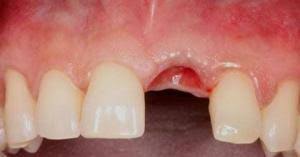

When lying down, prop your head with pillows. The total tooth extraction healing time depends on the location of the tooth and the type of extraction performed, but you can expect it to fully heal it's helpful to look at tooth extraction healing pictures that correspond to the stage you're to get a better idea of what the extraction site should look like. Have you been wanting to improve your confidence in oral surgery and extract more teeth? Natural remedies for pain following a dental extraction can bring a surprising amount of pain relief, without the risk of side effects from prescription pain medication. Getting a tooth pulled tooth extraction healing and recovery tooth extraction complications.

Once your tooth's extraction procedure has been completed, you'll no doubt want to know how long it will take for its socket to heal. Tooth extraction healing in bone tissue. Here are some remedies for tooth extraction healing. Getting a tooth pulled tooth extraction healing and recovery tooth extraction complications. Pulling teeth due to damage or decay: Following a tooth extraction or oral surgery, significant pain is not uncommon. The initial healing of the extraction site (the socket) usually takes from 1 to 2 weeks, depending on the complexity of the. Natural remedies for pain following a dental extraction can bring a surprising amount of pain relief, without the risk of side effects from prescription pain medication.

There may be several reasons why you need to get a tooth extracted. It is normal to have slight bleeding (oozing) from the site considering the surgical procedure performed. Tooth extraction healing timeline how long does it take for bone and gums to heal pictures. Tooth extraction, especially for a wisdom tooth, can feel like an unending road of pain. Once your tooth's extraction procedure has been completed, you'll no doubt want to know how long it will take for its socket to heal.